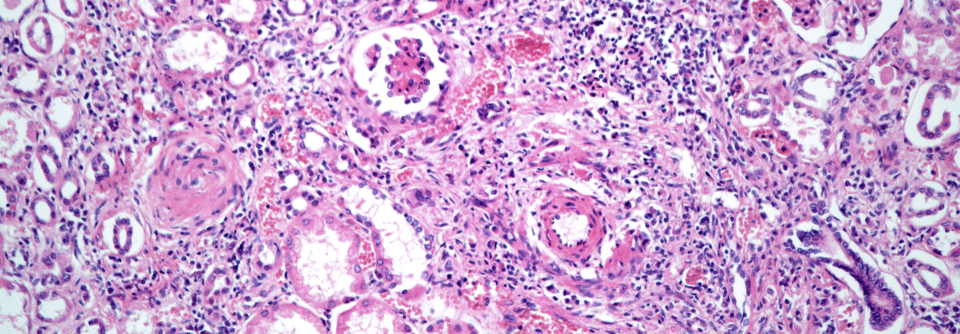

Eosinophilen, große Parasiten abzutöten. Manchmal geht der Schuss aber nach hinten los. Der zerstörerische Inhalt ermöglicht es Eosinophilen, große Parasiten abzutöten. Manchmal geht der Schuss aber nach hinten los. © iStock.com/Dr_Microbe

Eine 55-jährige Asthmatikerin suchte wegen chronischer Müdigkeit, Abgeschlagenheit, Myalgien und rezidivierenden Hautläsionen die Klinik für Innere Medizin des Kantonsspitals in Münsterlingen auf. Bei der klinischen Untersuchung zeigten sich neben obstruktiven Atemgeräuschen ca. 5 mm große, teilweise erhabene, livide Läsionen im Bereich der Unterschenkel, die weder schmerzhaft noch wegdrückbar waren. Im Labor fielen eine ausgeprägte Eosinophilie (11 G/l), eine Anämie (Hb 70 g/l) sowie eine humorale Entzündungsaktivität auf.